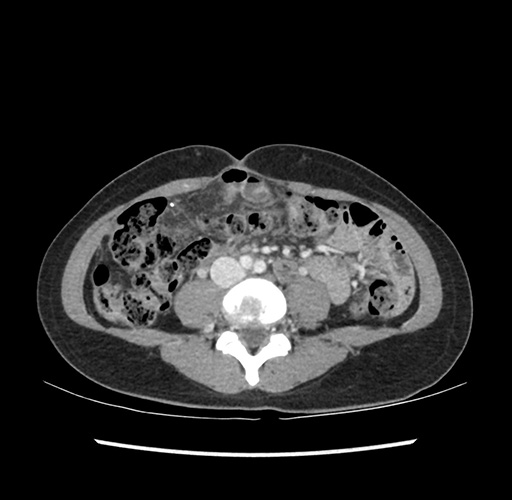

Imaging Analysis

Look through the patient's CT scan to identify any areas of concern for the necessary procedure.

Based on your CT findings, which issue(s) would give reason for "planned slowing down moment(s)" in this case?

Considering a standard left lateral sectionectomy procedure, what step(s) of the operation would you do differently in this case ?